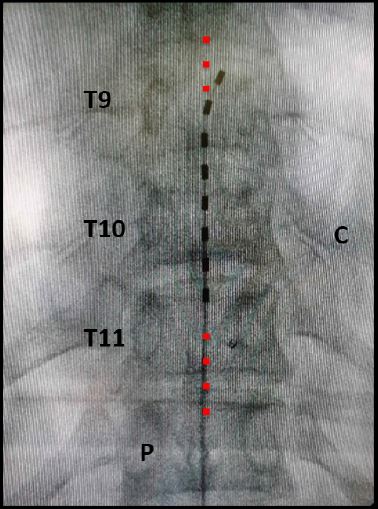

Paso 1. Planeación. Una vez el paciente se encuentra bajo anestesia local asistida o general y en posición de decúbito prono, se verifica que no haya zonas de presión y se colocan soportes que permitan dejar libre el tórax y el abdomen, para no aumentar la presión intratorácica o intrabdominal. La planeación se hace antes de la asepsia y la antisepsia, utilizando visión de fluoroscopia (rayos X) y se debe identificar en la piel el punto de entrada sobre el borde inferior del pedículo opuesto al lado que se desea estimular. Si la estimulación es bilateral, se escogerá el lado que se facilite, de acuerdo con la mano dominante del cirujano (cirujano diestro: pedículo izquierdo; cirujano zurdo: pedículo derecho). Se selecciona el punto de entrada de la aguja en el espacio epidural, lo que permite determinar la dirección de la punción y el ángulo con respecto a la piel, que debe corresponder con el borde inferior de la apófisis espinosa. Igualmente, se selecciona la posición del bolsillo en el que va alojado el generador de pulso y a través del cual se va a realizar la punción. Este bolsillo no debe ir en contacto estrecho con superficies óseas. Esta planeación es muy importante, sobre todo, en aquellos pacientes ya operados de la columna o con material de instrumentación que limita y hace más compleja la implantación ( figura 7).

Paso 3. Implantación del electrodo y navegación del espacio epidural. Se introduce el electrodo a través de la aguja y se navega por el espacio epidural hasta colocarlo en el sitio determinado durante la planeación. Se debe verificar la posición del electrodo con proyecciones anteroposteriores y laterales del arco en C mediante fluoroscopia (rayos X). Si se está en la fase de prueba, la posición del electrodo será determinada por la presencia de parestesias que el paciente despierto va a ubicar en la zona del dolor. Si se está en la fase definitiva, la posición del electrodo será determinada por el análisis de la posición del electrodo en la fase de prueba y de los contactos que permitieron una mejoría del dolor ( figura 9).